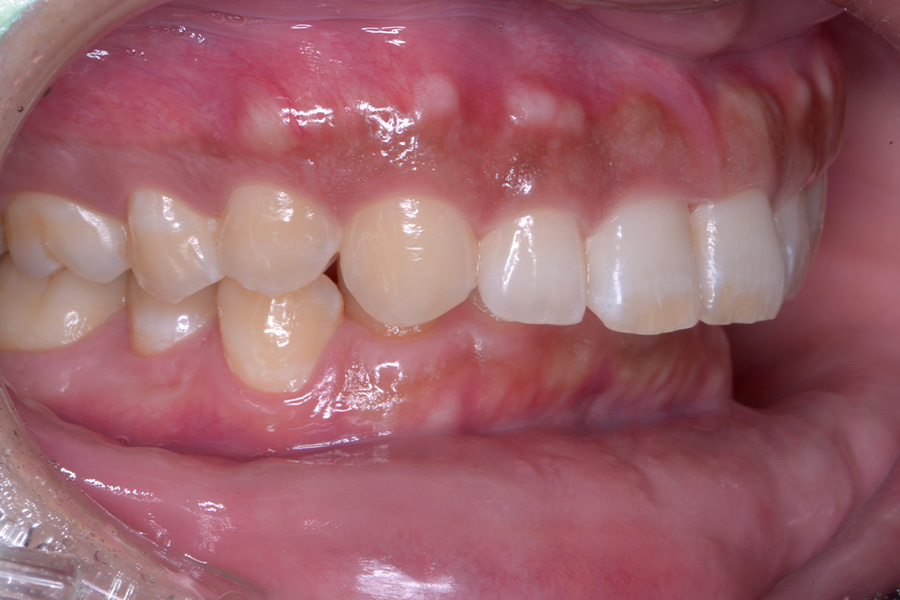

治療前

主訴 捻じれている歯を引っ込めたい

治療内容 上顎リンガル矯正(裏側矯正)